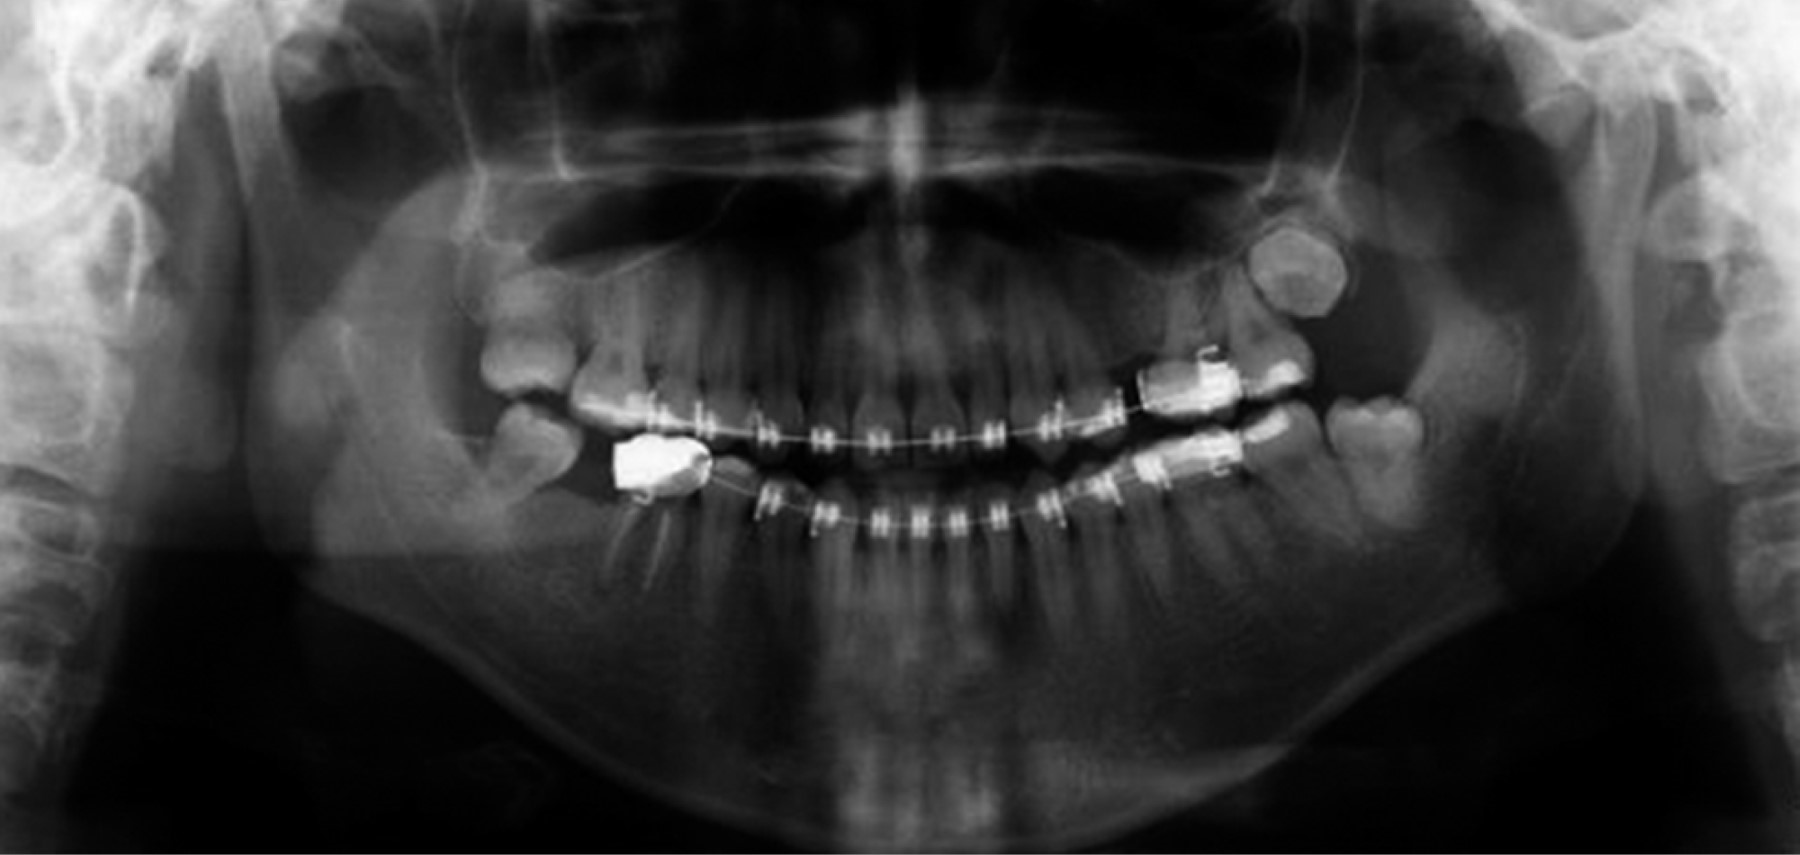

Orthopantomography was taken to verify radicular parallelism, and control of the osteosynthesis material (Figure 10). The patient continued using elastics to correct muscular patterns of occlusal settlement. Consultation was made with the Department of Periodontics, DEPeI, UNAM, for the future placement of dental implants, where they told us to have an adequate space of 7 mm for the upper left premolar (Figure 11).

Figure 10

Figure 11